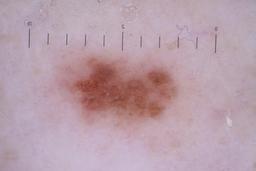

ISIC_6742970

- Sydney Melanoma Diagnostic Center at Royal Prince Alfred Hospital, Pascale Guitera

- Challenge 2020: Training

Clinical

| Field | Value |

|---|---|

| acquisition_day | 91 |

| age_approx | 75 |

| anatom_site_1 | Trunk |

| anatom_site_2 | Posterior trunk |

| concomitant_biopsy | False |

| diagnosis_1 | Benign |

| diagnosis_confirm_type | serial imaging showing no change |

| fitzpatrick_skin_type | I |

| image_type | dermoscopic |

| lesion_id | IL_7403129 |

| patient_id | IP_4261345 |

| sex | male |